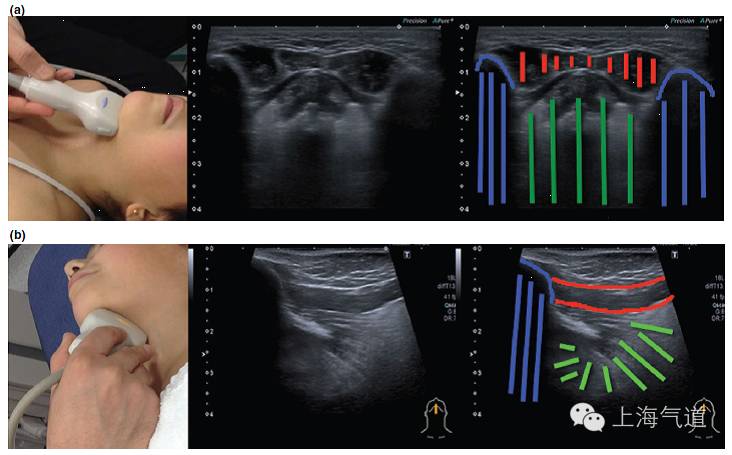

图2a. 将探头置于颏下区取横断面,绿色区域为舌体,红色为口腔内肌肉组织,蓝色为下颌骨及其伪影。b.将探头旋转90度并置于中线位置,取此区域的长轴影像

图3 a. 探头置于下颌骨水平取纵断面,黄色为颌下腺,红色为颈外动脉,棕色为扁桃体。b. 将探头旋转90度所得此区域的影像